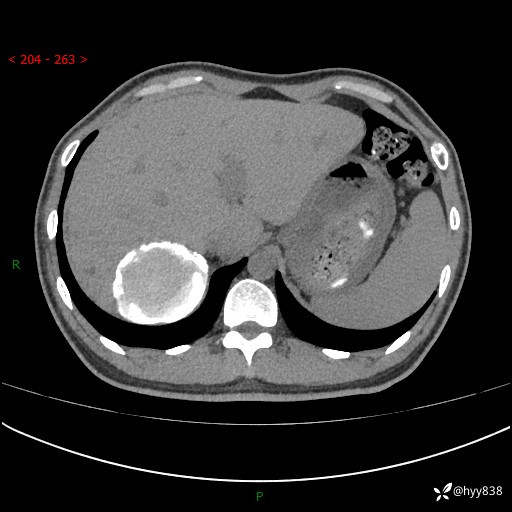

性别:男

年龄:50岁

简要病史:夜尿增多半月,发现肾功能异常1天,超声发现腹膜后占位

腹部CT平扫+增强